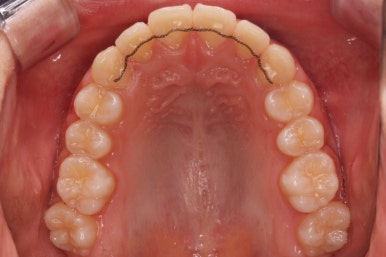

처음 내원 때의 입안 모습입니다.

영구치는 모두 맹출이 되어있었고 아랫니는 윗니에 비해 매우 가지런한 편이였습니다.

윗니 중에서도 앞니가 매우 삐뚤하고 특히 작은 앞니 양쪽 모두가 아래 앞니보다 안쪽에 들어가 있는 모습입니다.